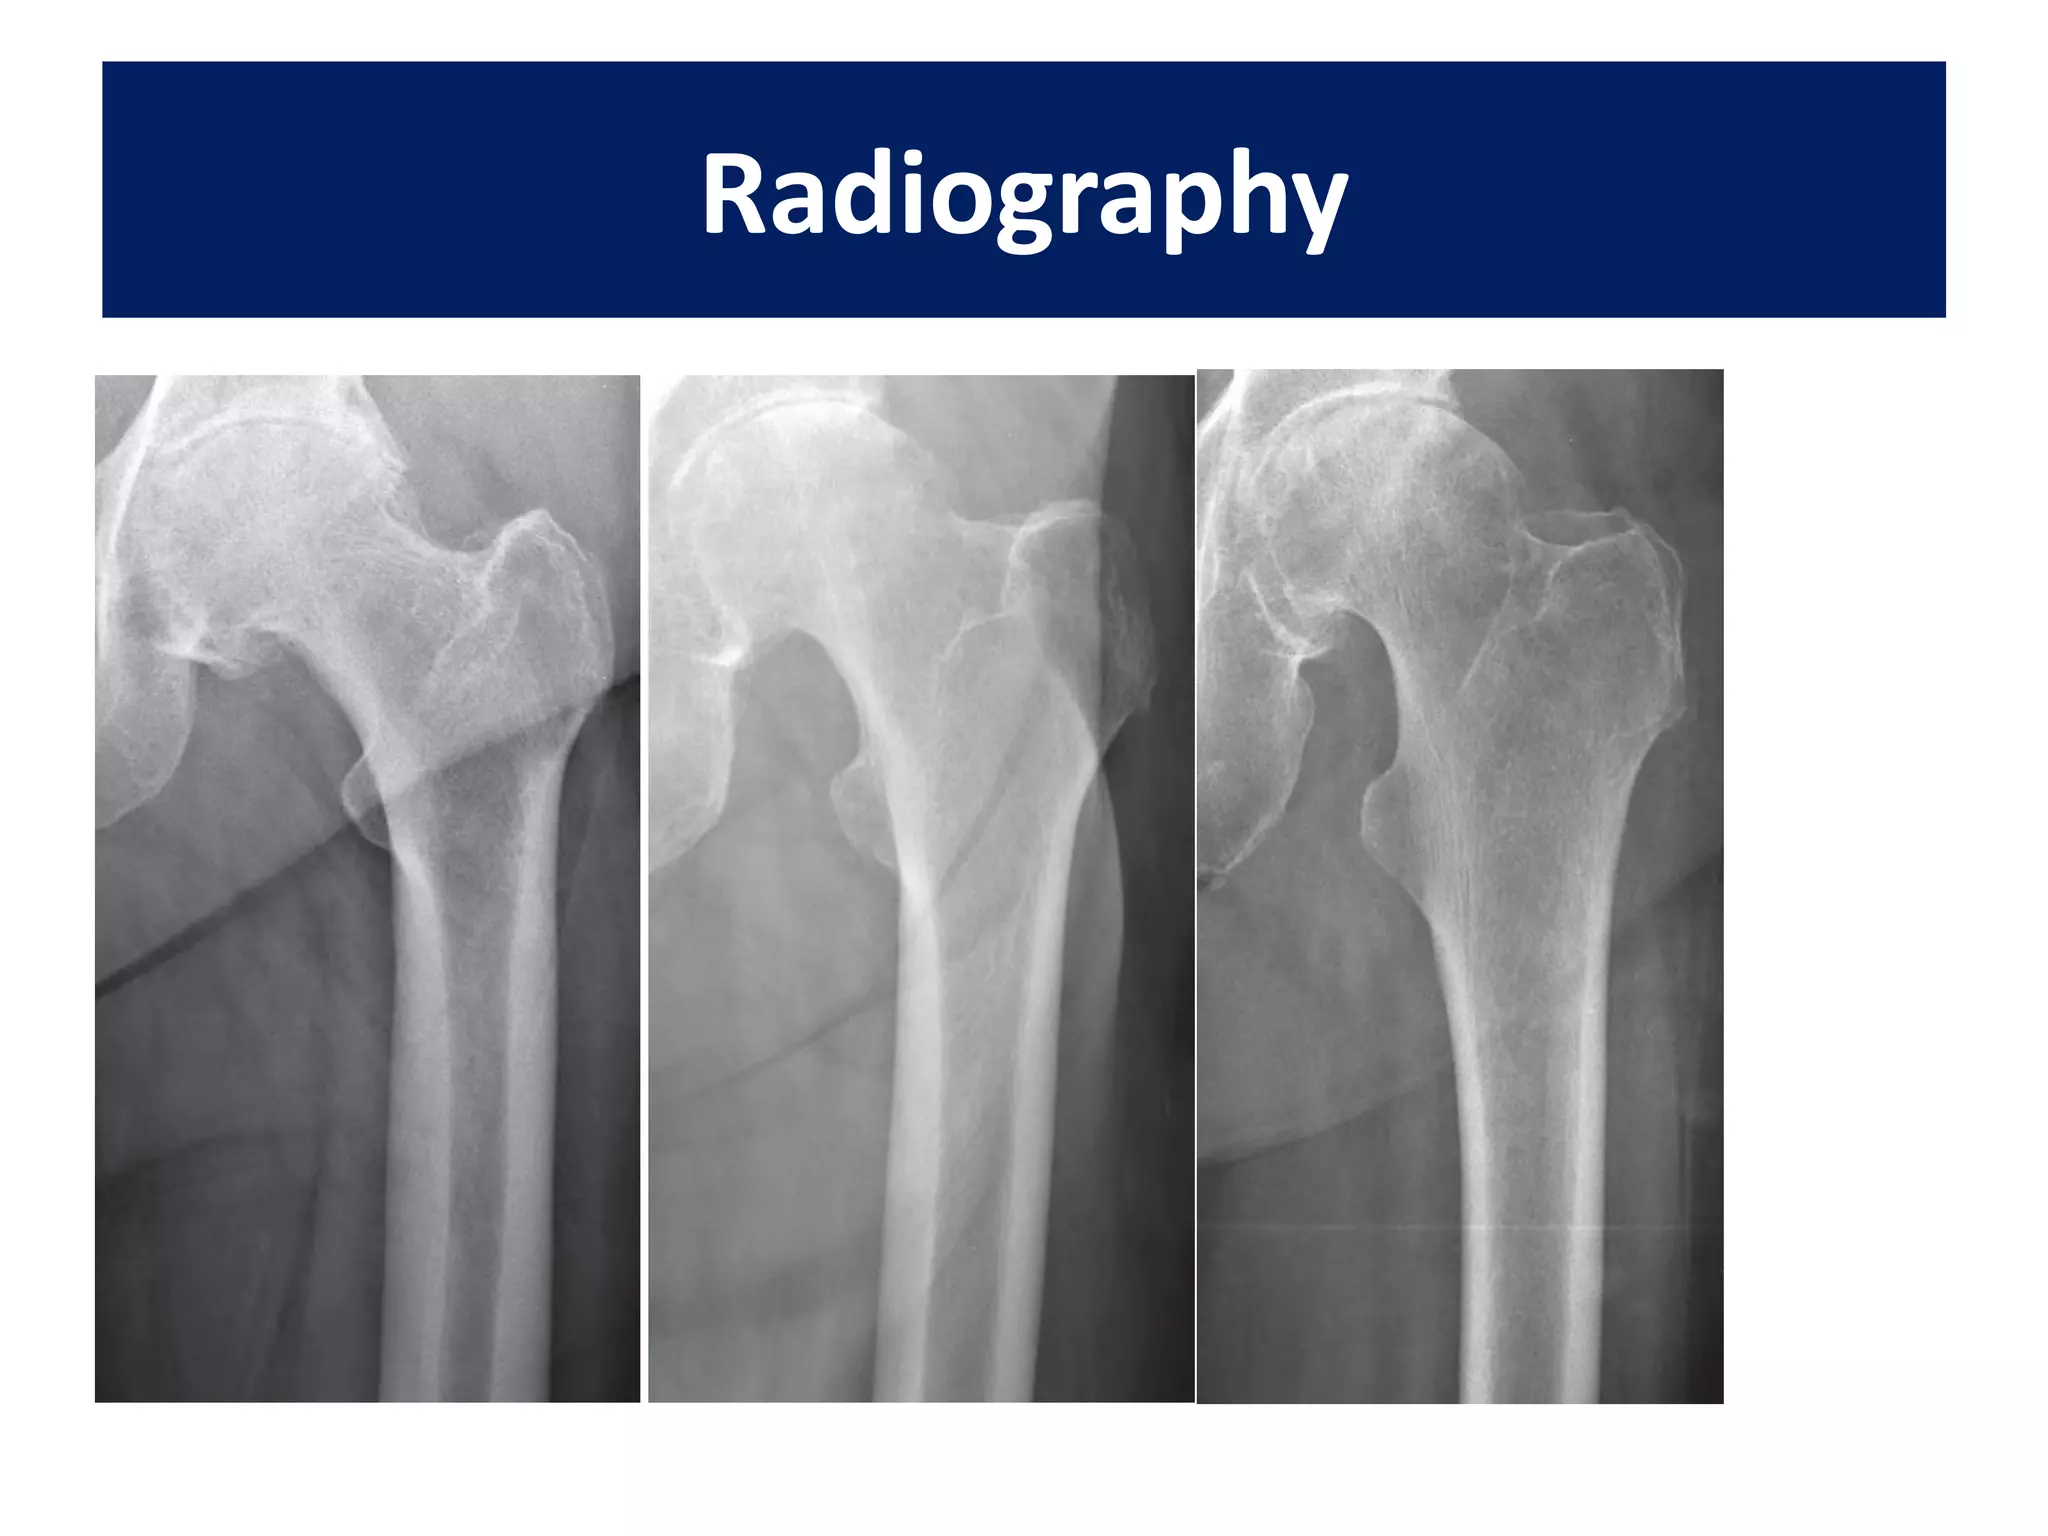

Radiographs should include

• an anteroposterior (AP) view of the pelvis,

• A full length AP and lateral films of the femur

• Traction views.

Radiography